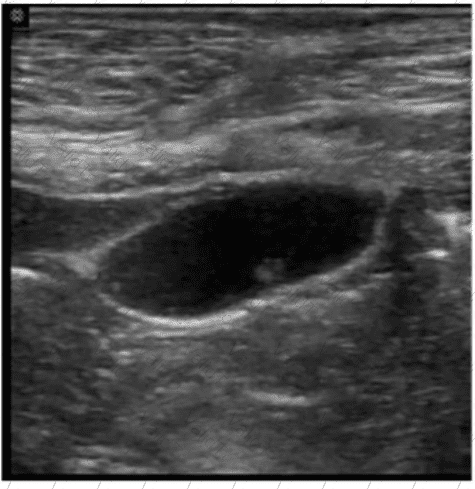

Which liver neoplasm is associated with use of oral contraceptives and is most often seen in women under the age of 40?